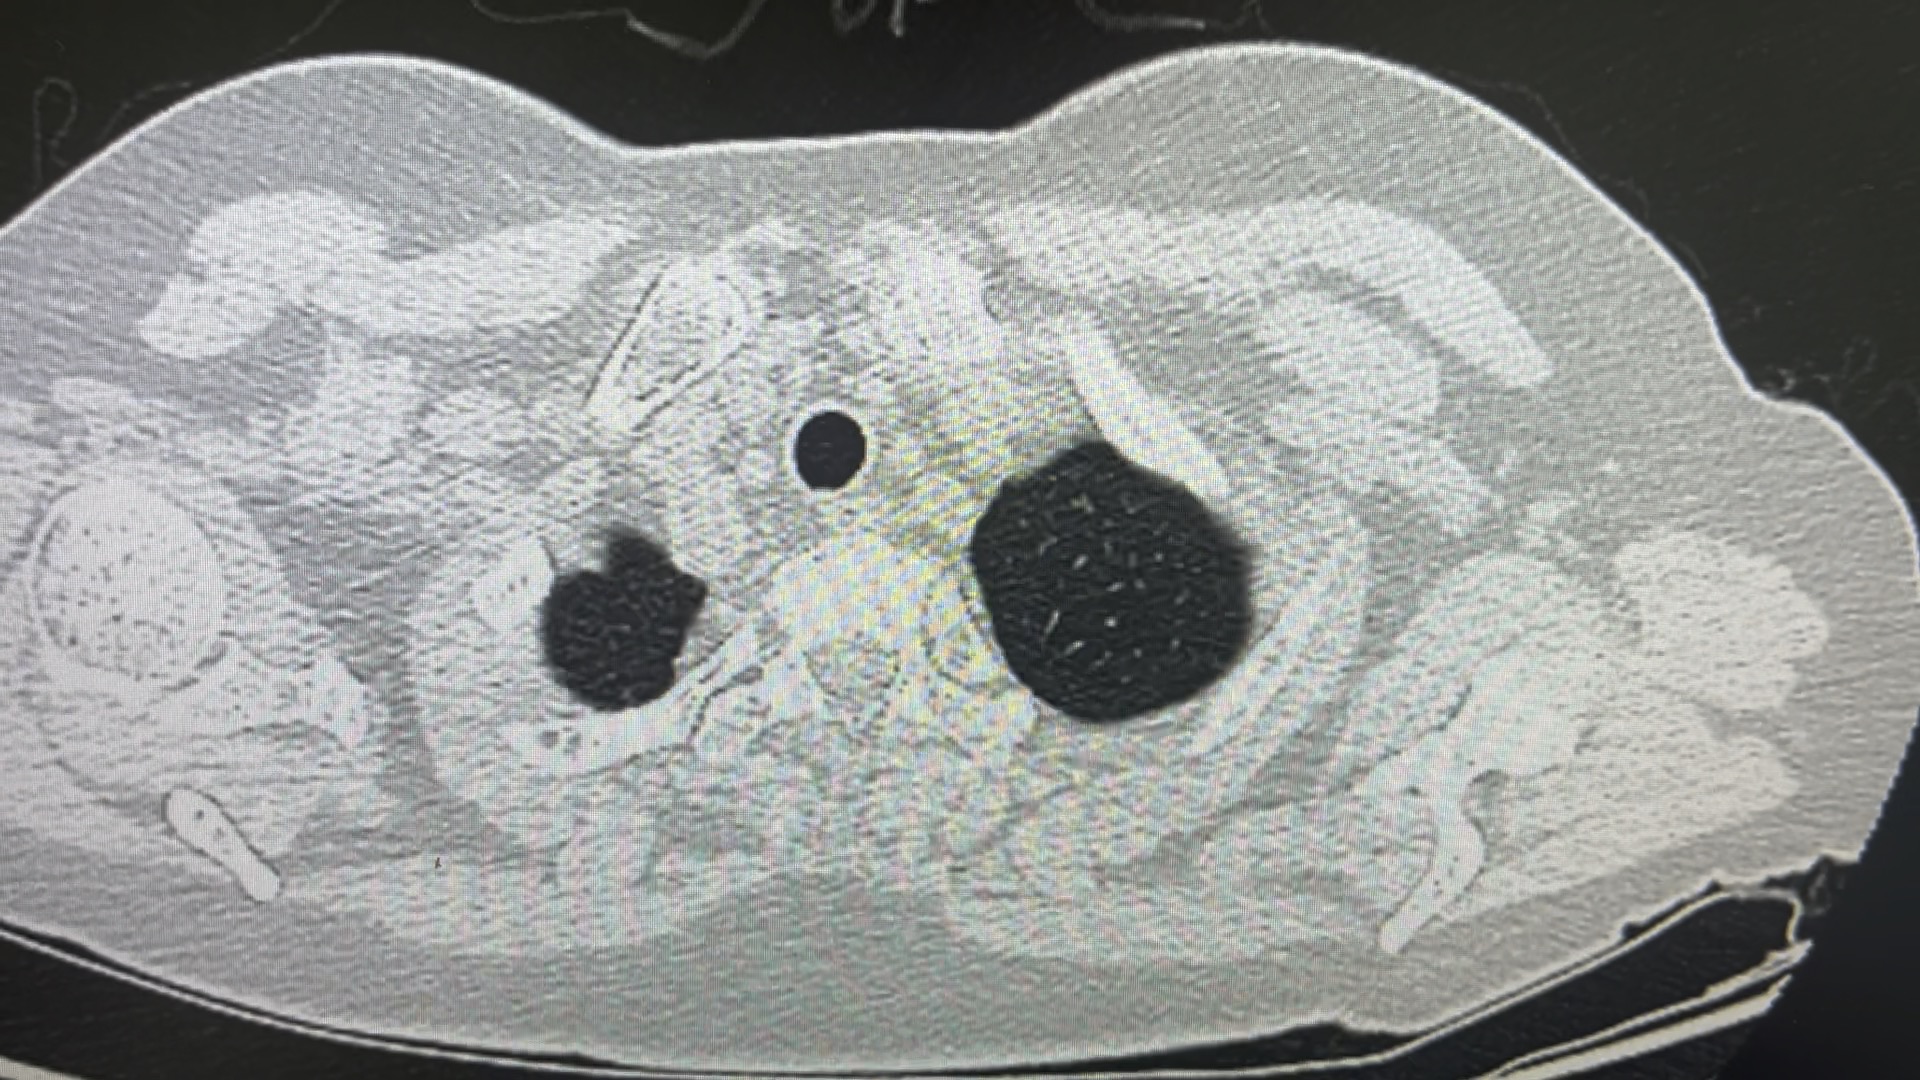

右肺两处明显病灶,分别位于右肺上叶后段和右肺下叶背段。手术拟行联合肺段切除术。由于这两处肿瘤在空间位置上很近,从二维CT来看甚至有共干的动脉,因此手术操作过程可节省部分解剖时间。

以下结合二维影像对肺段解剖结构进行分析。肺段解剖变异较多,单纯依靠二维CT辨别解剖结构是一件非常烧脑的事情,尤其是对于初学者。但是熟能生巧,只有经常训练二维影像阅片的能力,才可以到达“一眼看清关键要点”的境界。我会花费一个多小时的时间从二维影像上来来回回反复阅览同一个病人的肺段解剖,辨认细节变异,都辨认清楚后确实会有些成就感和通透感。

首先映入眼帘的是肺裂发育不佳。只在肺表面有些许裂痕,靠近肺门区域肺裂消失,提示手术解剖肺裂将会比较困难。

右肺上叶后段结节,位于B2a远端。

这是后升支动脉,远端发出两个分叉,汇入处和中心静脉毗邻很近

这是下叶背段动脉,和上叶后段动脉共干发出